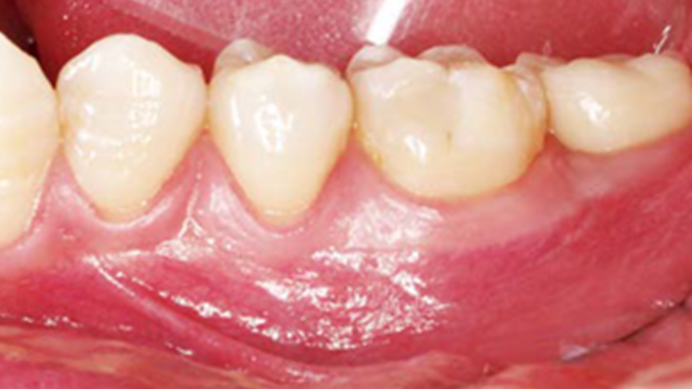

Clinical case: Single molar implant with bone augmentation

- Courtesy of Dr. Jung Sam Lee, Korea -

Keywords

AnyOne, bone augmentation, osteotomy socket, peri-implant tissue, autogenous bone, GBR, single replacement, Auto-Max, Dr. Jung Sam Lee

Products:

AnyOne implant system, Auto-Max